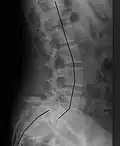

Radiografía de medición de espondilolistesis en la articulación lumbosacra, siendo el 25% en este ejemplo. -

Clasificación por grado de deslizamiento, medido como porcentaje del ancho del cuerpo vertebral:[14] La espondilolistesis de grado I representa aproximadamente el 75 % de todos los casos.[15]

- Grado I: 0–25%

- Grado II: 25- 50%

- Grado III: 50–75%

- Grado IV: 75–100%

- Grado V: superior al 100%